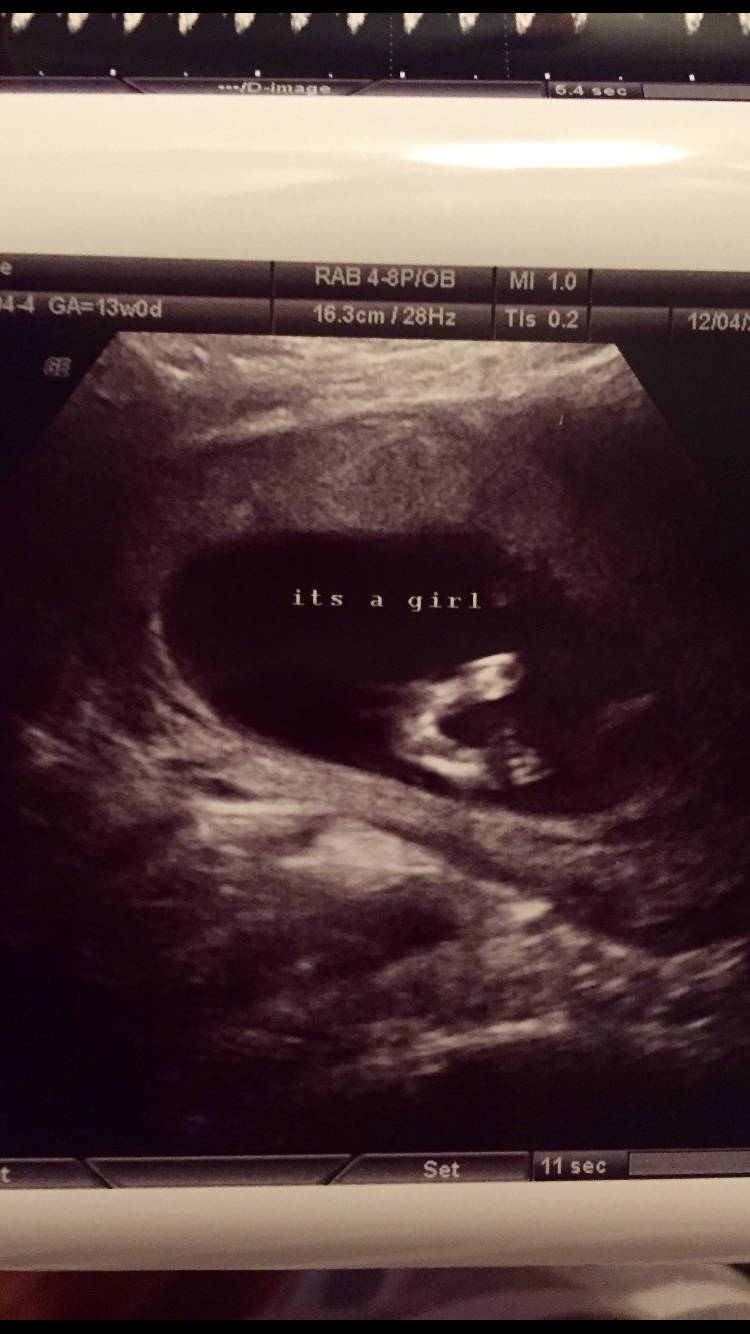

• I went for a 14 week US to the exact date and the tech said she was 101% sure. She wrote "It's a girl!" All over our pictures. :) I'm not a professional US tech (but am an RN) but from the shots I saw .. I'd definitely agree with her on girl. I would, however, probably think 12 weeks is too early to tell. I second the everyone updating at 20 weeks!